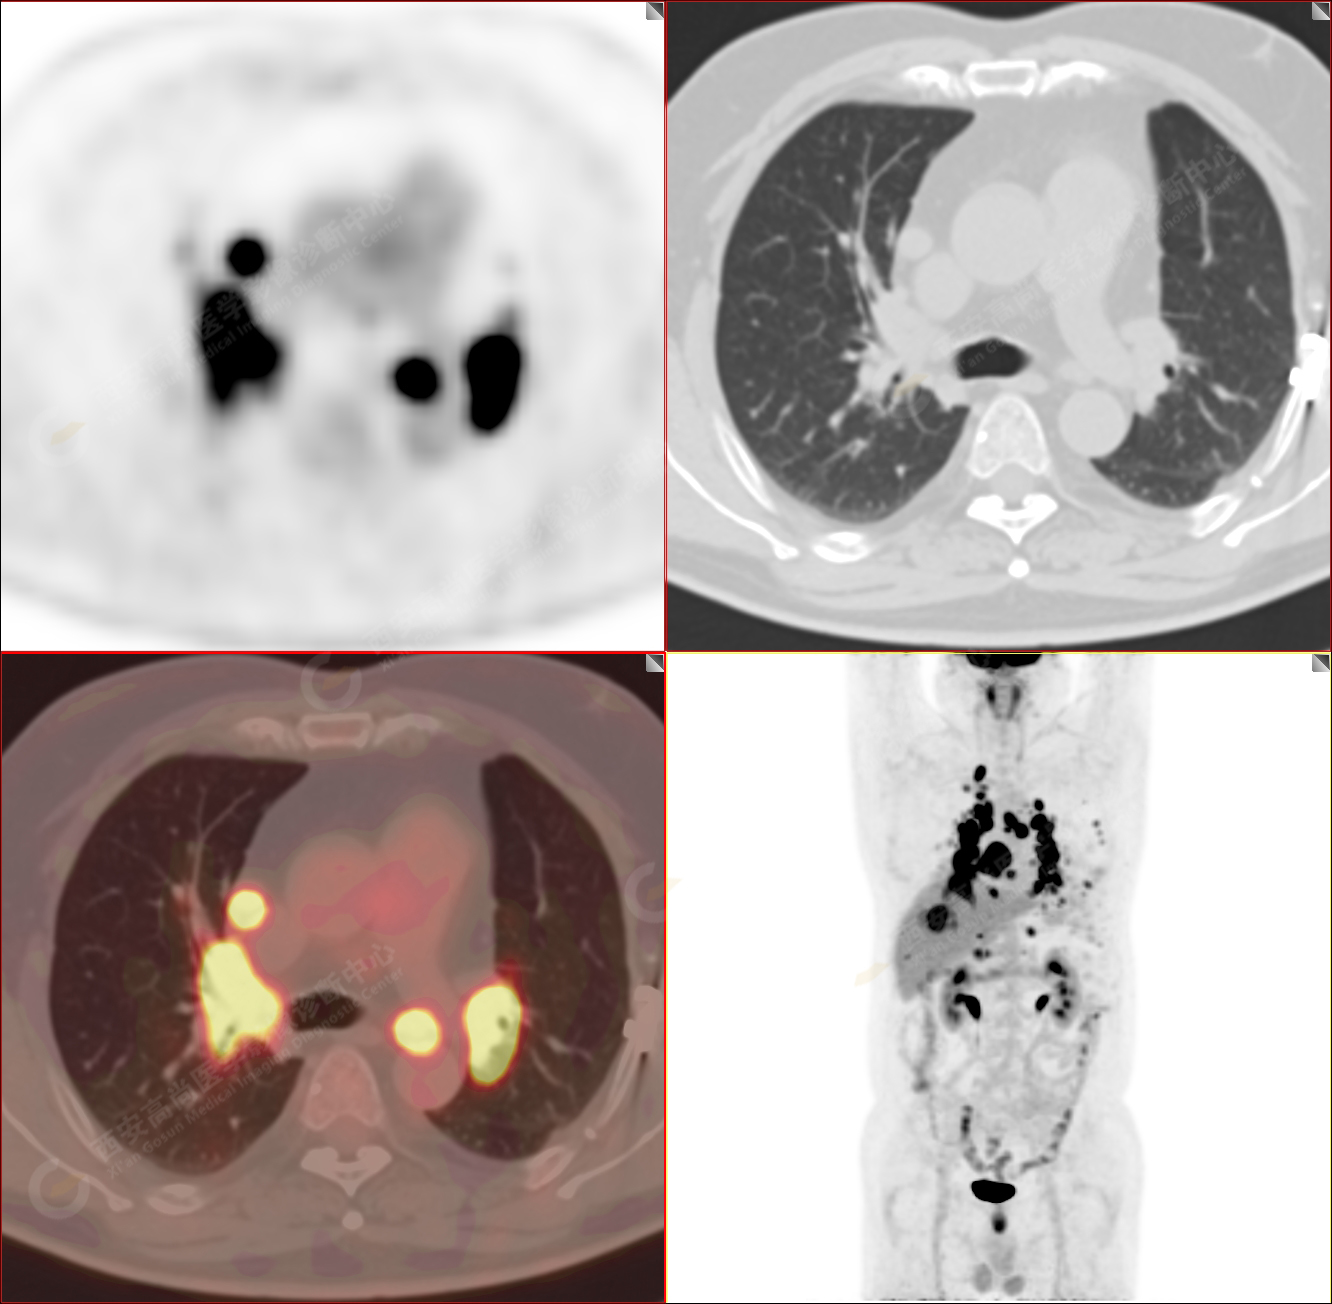

男性,53歲,頭暈半月入院,CT發(fā)現(xiàn)肺內(nèi)腫塊,雙肺多發(fā)大小不等實(shí)性及粟粒樣結(jié)節(jié),雙肺門(mén)及縱隔多發(fā)腫大淋巴結(jié)。病程中無(wú)發(fā)熱、胸悶氣及胸部不適。既往:左側(cè)肋骨外傷史。

PET/CT圖像